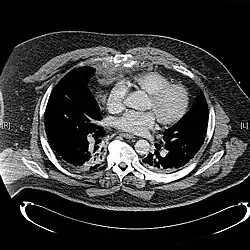

Сверху: грудина окрашена цветом морской волны. Внизу: компьютерная томограмма оскольчатого перелома грудины.[1] | |